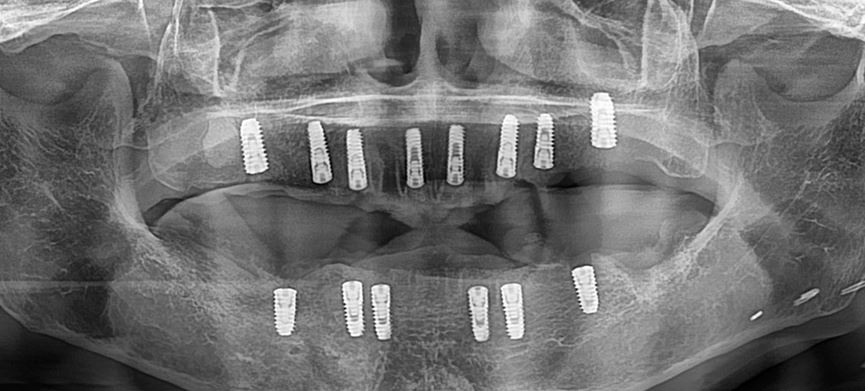

하악 전체 임플란트 식립

2주 정도 후에 하악 전체 임플란트 진행

(수술 시간은 약 1시간 소요)